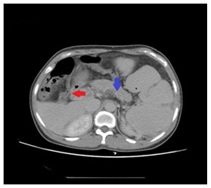

A 51 year old woman suffered from a first episode of fresh blood vomiting and discomfort of abdominal distention after 2 years working on spray paint in a private furniture factory in China mainland. Meanwhile, we don’t find any sign of swollen skin and other complications and she denied the feeling of itch. She repeatedly complained that her health went worse gradually since she began to work on spray paint, when compared to her previous medical health record. Hence, she highly suspected that her symptoms might be associated with her work environment or some paint solvents. She and her family hoped clinicians could confirm or exclude her suspicion during therapeutic course in this admission. Her words arouse our great interest and we decided to decode the conundrum. Amazingly, no specific clues were obtained from her family history, appetites and general laboratory tests. Further enhanced contrast computed tomography of abdomen showed special findings, including isolated gastric varices, major portal vein thrombosis (red arrowhead), focal splenic vein stenosis (blue arrowhead), and splenomegalia complied with focal splenic, but myelofibrosis was confirmed by bone marrow biopsy and the expression of JAK2-V617F was detected in her peripheral blood sample (Figure 1).

Figure 1: Special findings, including isolated gastric varices, major portal vein thrombosis (red arrowhead), focal splenic vein stenosis (blue arrowhead) and splenomegaly complicated with focal splenic.